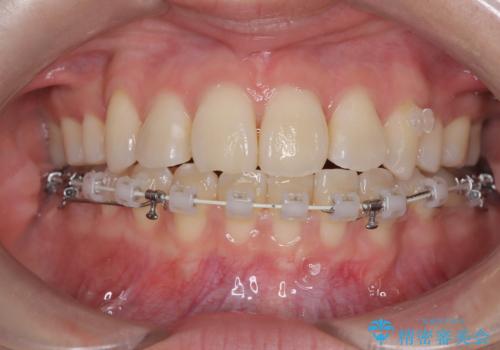

ハーフリンガル矯正|下顎前歯3本の特異症例を抜歯矯正で改善

- 患者様は下顎の前歯が3本しかないという特異な歯列を持ち、噛み合わせのバランスが崩れていました。上下の歯の本数が通常と異なるため、抜歯部位の選定が重要となるケースでした。診査の結果、歯の位置や咬合のバランスを考慮し、上顎の両側小臼歯2本と左下の小臼歯1本を抜歯することで、上下の噛み合わせを整える方針としました。矯正装置は、**目立ちにくいハーフリンガル(上顎は裏側矯正・下顎は表側矯正)**を採用しました。

まず、計画通りに抜歯を行い、歯列のスペースを確保しました。上顎は裏側矯正(リンガル)で目立たないように配慮しながら歯を後方へ移動し、下顎は表側矯正を使用して、3本の前歯の位置関係を調整。上下の歯の噛み合わせを細かくコントロールしながら、全体のバランスを整えました。治療後は「歯並びがきれいになり、噛み合わせもしっかり合うようになった」と患者様にも満足していただけました。